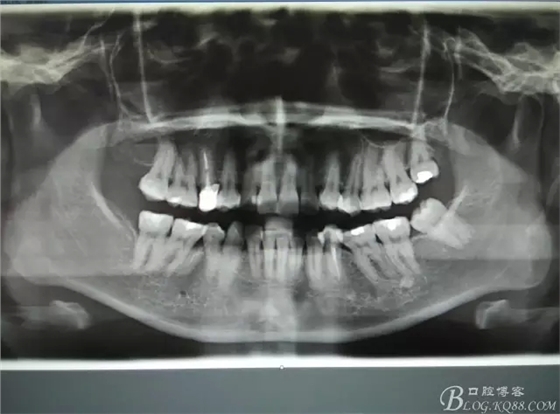

圖1.患者術(shù)前的全景片、側(cè)位片影像檢查:45牙根位于44與46之間,44與46鄰接緊密